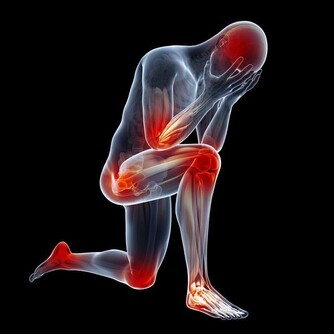

露腳踝易得踝關節炎現在很多年輕人把捲起褲腿或者穿短襪露出白皙纖細的腳腕當成一種時尚。但在醫生看來,這種看似時尚的穿著,最容易誘發踝關節炎。

東南大學附屬中大醫院中醫骨傷科主任屈留新解釋,腳踝部位分布著淋巴管、血管、神經等近十個重要的組織,被稱為人體的第二心臟,如果經常把腳踝露出來,不僅會引發踝關節炎,還會使抗病能力下降而導致感冒。

另外,東南大學附屬中大醫院中醫骨科副主任醫師陸軍說,腳踝承受著全身的重量,是人體比較脆弱的地方,對外傷缺乏緩衝,很容易受到各種傷害。再加上踝關節周圍軟組織少,局部血液循環較差,如果再不穿襪子加以保護,很容易著涼而引發疾病。而能不能露腳踝,還要看個人體質,不要盲目去效仿。

膝關節:預防老寒腿很多年輕女性喜歡短裙,膝關節長期暴露在寒冷的環境中,會引起血液循環不通暢,導致老寒腿,出現腿部酸麻脹痛而且還有沉重感。